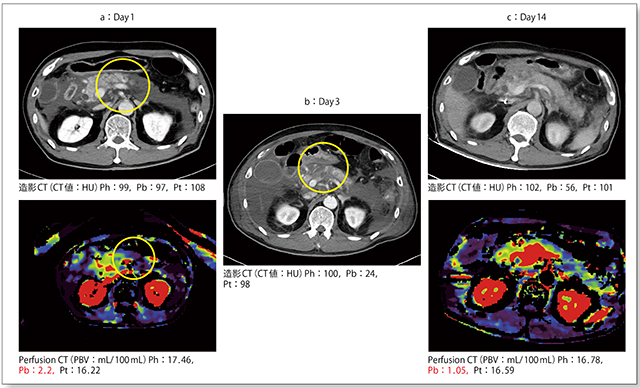

入院時の造影CTでは,腎下極以遠への炎症波及を認めるが,明らかな造影不良域は確認できず,CT値もすべて100HU前後で虚血は確認できなかった(図2 a上)。しかし,Whole Pancreatic Perfusion CTを施行したところ,カラーマップにて膵体部に虚血を示す所見が認められ,perfused blood volume(PBV)の値も膵頭部,膵尾部に比べて膵体部ではかなり低下していた(図2 a下)。

第3病日に再度造影CTを施行すると,入院時のWhole Pancreatic Perfusion CTの虚血域と一致して膵体部に明らかな造影不良域が出現しており(図2 b),造影CTではわからないような虚血も,Perfusion CTにて同定可能であることが確認できる。

本症例は壊死性膵炎と判断し,第3病日から膵動注療法を開始した。血中のCRP(C反応性蛋白)値は最大30mg/dLと,かなり強い炎症があったが,第14病日には炎症は明らかに陰転化していた。同日の造影CTでは,膵実質壊死から膵局所合併症,膵膿瘍を形成した部分が黒く反転しており,膵体部のCT値は56HUとかなり低値であった(図2 c上)。Whole Pancreatic Perfusion CTでも膵体部が黒く反転しており,膵虚血を呈していることがわかる(図2 c下)。

図2 症例1:造影CTとWhole Pancreatic Perfusion CT所見